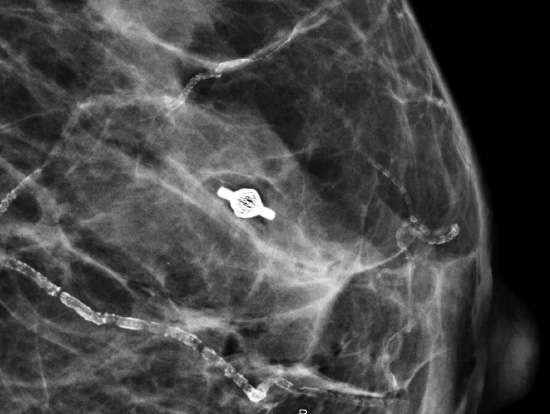

Clipmarkierung

Tumark® Vision Atlas

Fallbeispiele

Der Tumark Vision Atlas enthält Fallbeispiele zu unserem Tumark Vision Clipmarker in der klinischen Anwendung. Die langfristige Sichtbarkeit des Clipmarkers ist vor allem bei der neoadjuvanten Chemotherapie von Bedeutung. Einige der Fallbeispiele informieren auch zu diesem Anwendungsszenario.